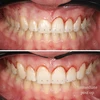

Zirkonyum uygulamalar

Porselen uygulamaları

Laminate veneer